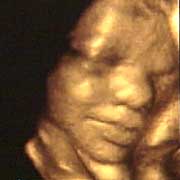

圖文:胎兒子宮內(nèi)表情豐富 專家稱提供研究新依據(jù)

中新網(wǎng)9月13日電 英國(guó)天空新聞報(bào)道,英國(guó)科學(xué)家圖亞特·坎貝爾最近利用先進(jìn)的掃描技術(shù)清晰地拍下了孕婦子宮中胎兒的表情,透過他拍攝的照片,人們可以清楚的看到一個(gè)尚未降臨世間的小生命喜、怒、哀、樂的表情。

斯圖亞特.坎貝爾是倫敦著名的產(chǎn)科教授,他利用超聲掃描技術(shù)拍攝到了胎兒在子宮中打呵欠、眨眼、吮手指、哭泣甚至微笑的畫面,這些都為胎兒行為的研究提供了新的依據(jù),專家認(rèn)為,這一突破將推動(dòng)?jì)雰航】悼茖W(xué)的發(fā)展,包括對(duì)唐氏綜合癥等嬰幼兒疾病的診治將起到極大的推動(dòng)作用。

此前,醫(yī)學(xué)界一直認(rèn)為,嬰兒要到降生后才可以做出喜、怒、哀、樂的表情,要通過模仿母親才可以學(xué)會(huì)微笑。

坎貝爾教授說:“有個(gè)這種技術(shù),現(xiàn)在許多問題都可以進(jìn)行研究了。比如說,患有唐氏綜合癥的嬰兒和正常嬰兒的活動(dòng)方式是否一樣?胎兒是否因?yàn)楦吲d才笑?胎兒哭是否是因?yàn)樵谧訉m中受到打擾?既然我們都認(rèn)為子宮內(nèi)是一片黑暗,那胎兒為什么會(huì)眨眼呢?”(章田)